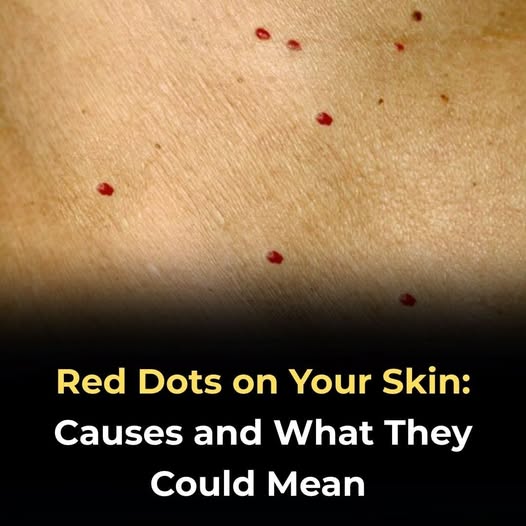

Whatever the reason behind a bite, it is important to handle the aftermath properly. Treating a cat bite should never be taken lightly. Because cats’ teeth are sharp and can puncture deeply, bacteria may be introduced under the skin, increasing the risk of infection. Immediately wash the wound with soap and water, apply antiseptic, and cover with a clean bandage. If the bite is deep, swollen, or painful, seek medical attention promptly.